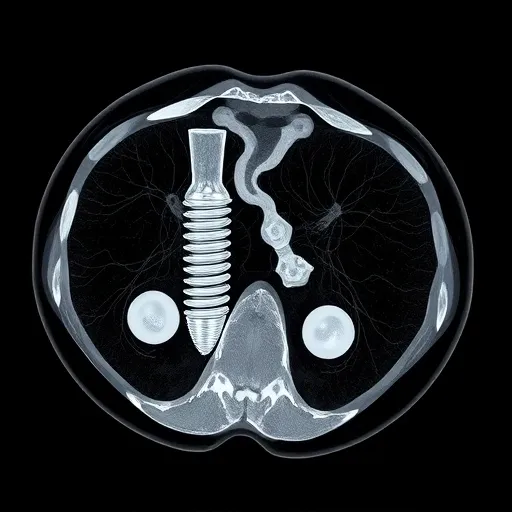

임플란트는 정밀한 시술이 핵심입니다. 과거의 아날로그 방식으로는 미세한 오차를 잡기 어렵습니다. 최신 트렌드는 디지털 임플란트로, 3D CT, 구강 스캐너, CAD/CAM 시스템 등의 첨단 장비를 활용합니다. 특히 3D CT는 잇몸뼈의 밀도와 폭, 신경관 위치를 입체적으로 파악하여 수술 계획의 정확도를 획기적으로 높입니다. 구강 스캐너는 인상채득 과정에서 발생하는 환자의 불편함을 최소화하고 보철물의 정밀도를 높이는 데 필수적입니다.

- 3D CT 장비: 뼈 상태와 신경 위치를 정확히 파악하여 안전한 경로를 확보.

| 3D CT (저선량) | 턱뼈 구조, 신경 위치, 뼈 밀도 분석 | 안전하고 정확한 식립 위치 결정 |

- 정밀 진단: 3D CT와 구강 스캐너로 환자의 구강 정보를 디지털화합니다.

뼈이식술은 상악동 거상술, 자가골 이식 등 다양한 방법이 있으며, 환자의 상태에 따라 가장 적합한 방법을 적용해야 합니다. 고난도 뼈이식은 치과 의사의 숙련도와 해부학적 지식이 절대적으로 필요합니다. 특히, 3D CT를 통해 뼈의 양과 위치를 정확히 파악하고, 이를 기반으로 뼈이식 계획을 세우는 병원이 신뢰도를 얻습니다.